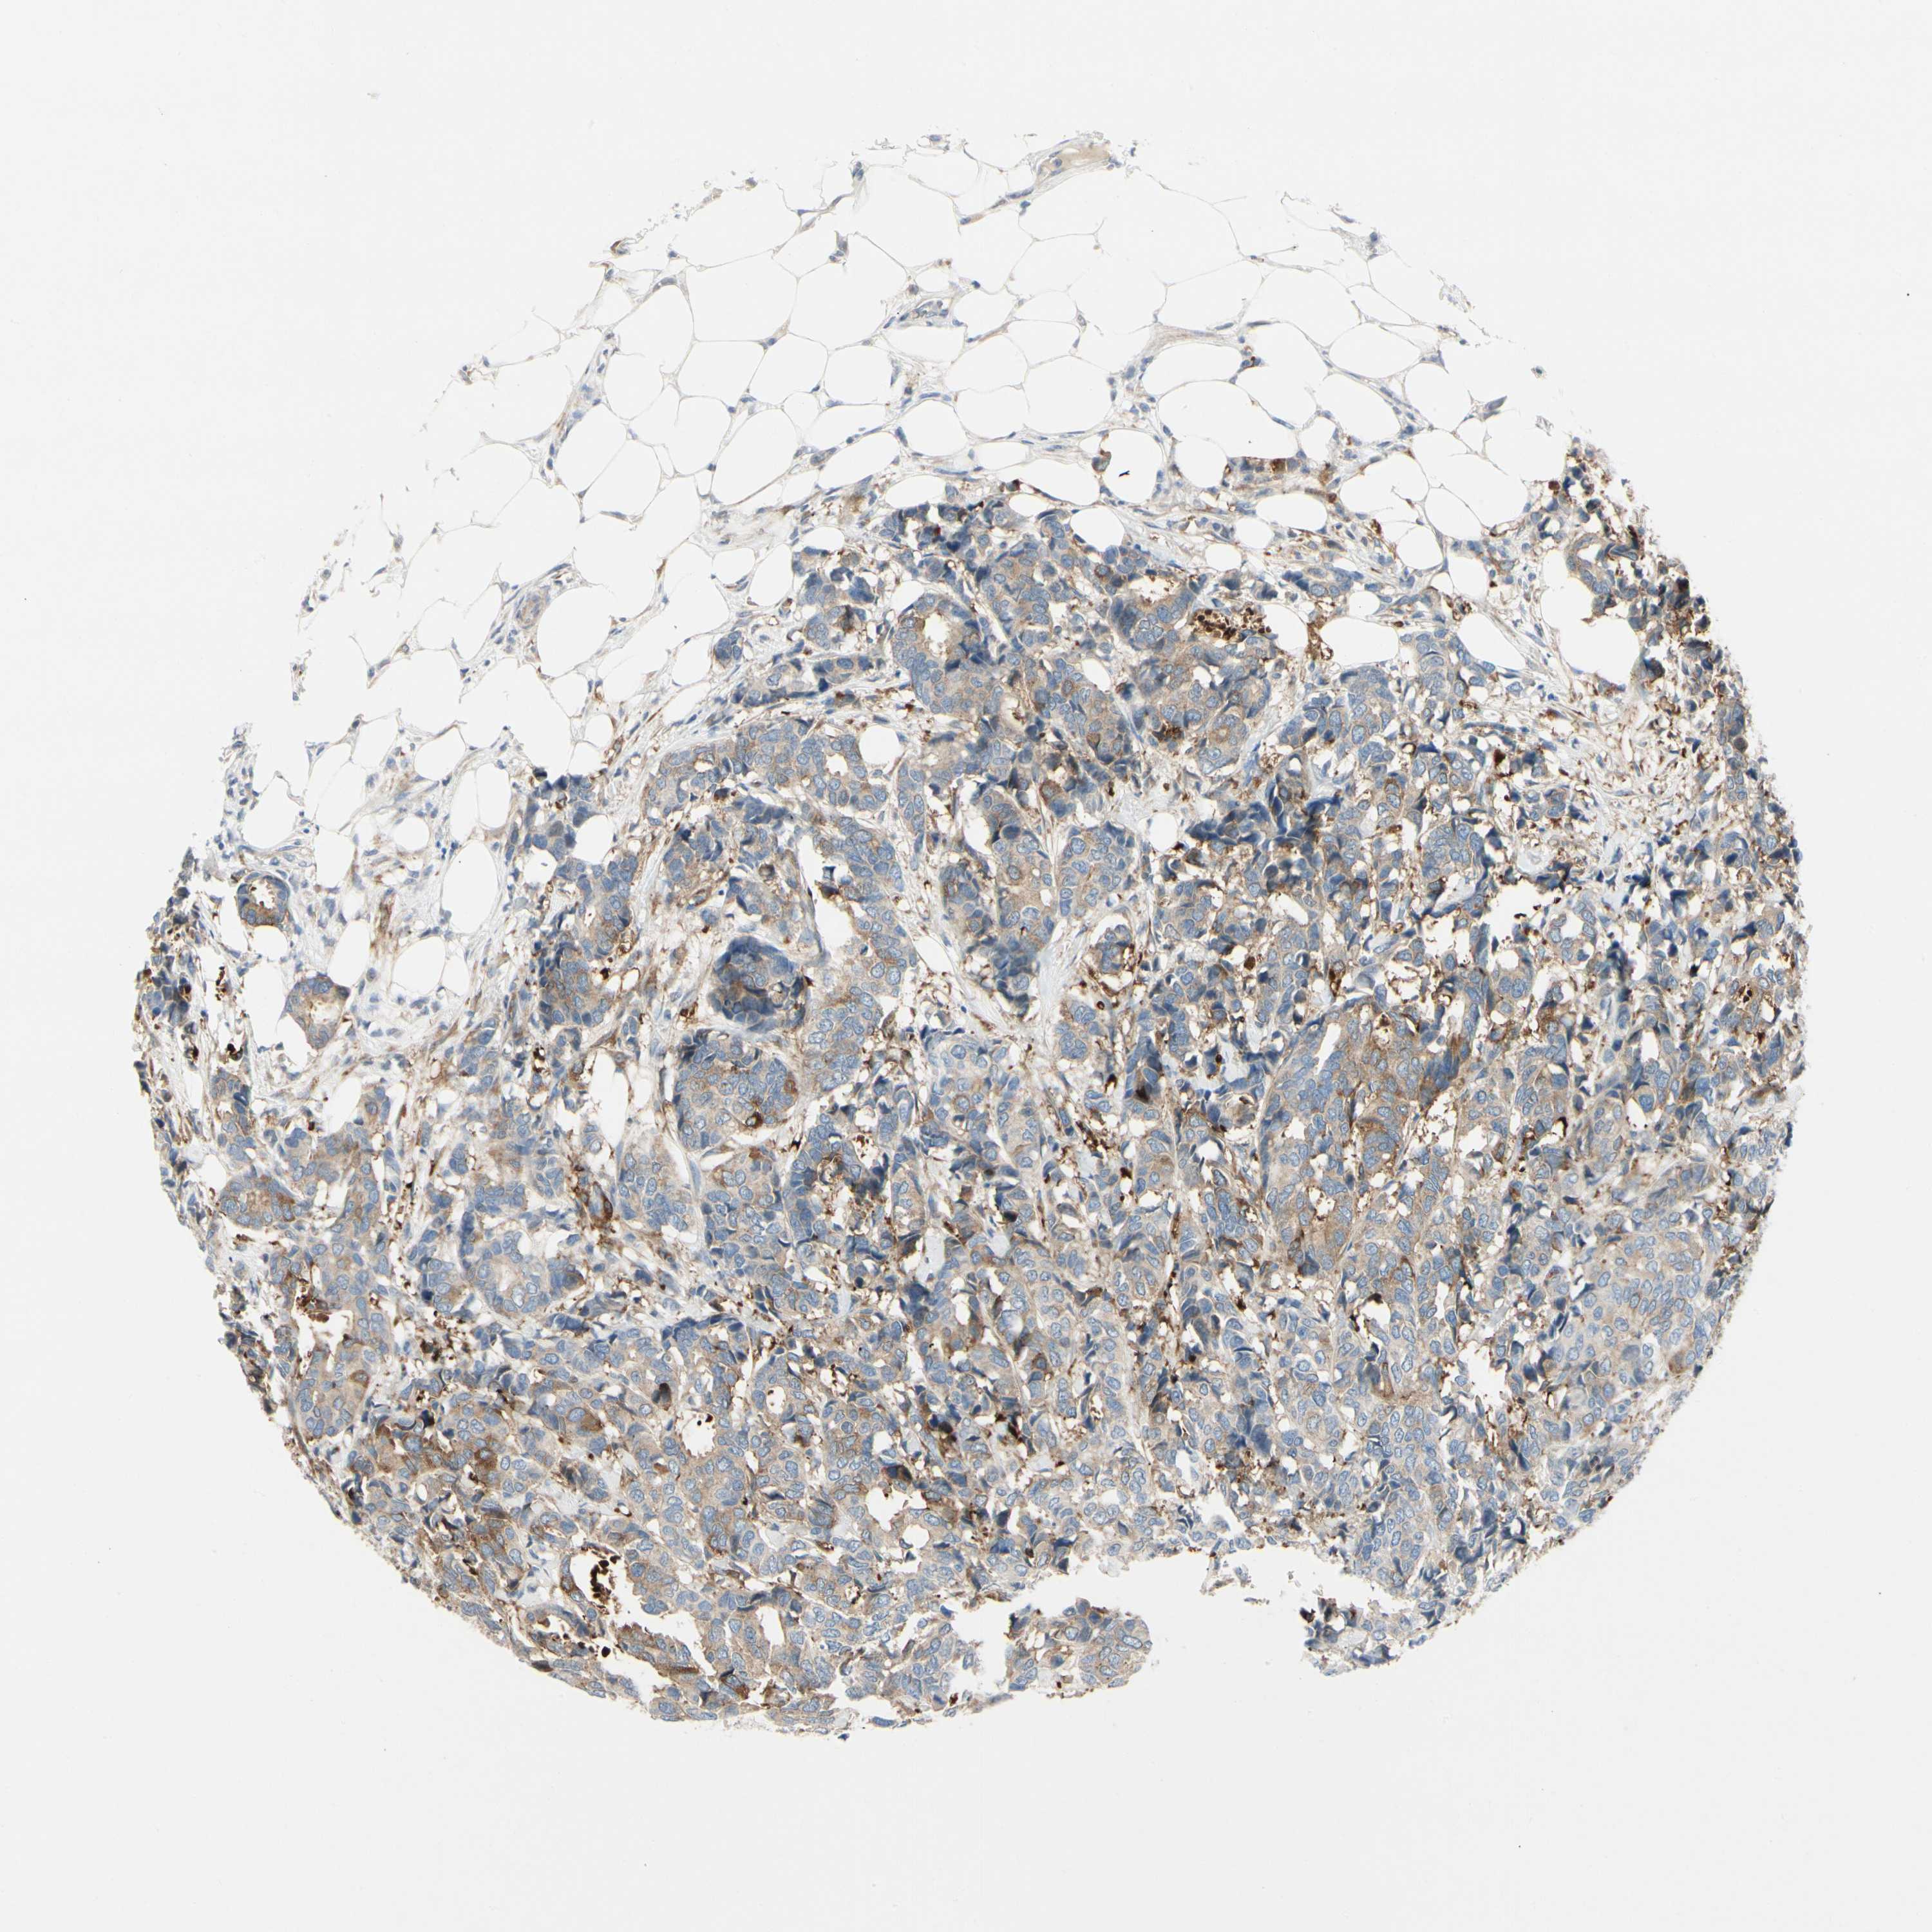

CANCER BREAST CANCER Show tissue menu

BRCA TCGA BRCA VALIDATION PROTEIN EXPRESSION

Breast cancer

Human cancer